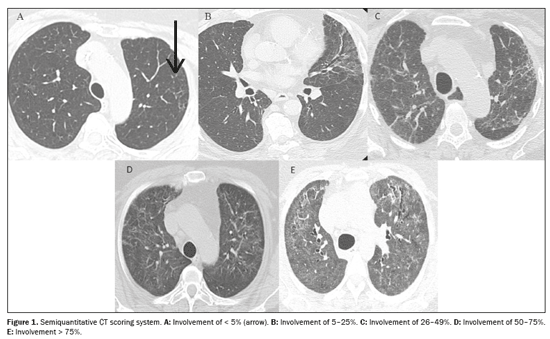

All of the images were evaluated by two thoracic radiologists with 8 and 12 years of experience, respectively, working independently; both were blinded to the clinical data and laboratory test results. Imaging characteristics were described as ground-glass opacities, reticular opacities, parenchymal bands, traction bronchiectasis/bronchiolectasis, and honeycombing, based on the standard glossary for thoracic imaging published by the Fleischner Society(15). Traction bronchiectasis/bronchiolectasis and honeycombing were further classified as fibrosis-like findings because they are associated with parenchymal distortion and irregular bronchopulmonary and pleuropulmonary interfaces(16). A semiquantitative scoring system(17) was used in order to assess the extent of lung involvement on chest CT scans. Each of the five lung lobes was visually scored on a scale of 0 to 5, with 0 indicating no involvement; 1 indicating involvement of < 5%; 2 indicating involvement of 5–25%; 3 indicating involvement of 26–49%; 4 indicating involvement of 50–75%; and 5 indicating involvement of > 75%. The total CT score was the sum of the individual lobar scores, therefore ranging from 0 (no involvement) to 25 (maximum involvement). Discrepancies between the two assessors regarding pulmonary findings were resolved by consensus. Figure 1 exemplifies the semiquantitative CT scoring system. The mean interobserver kappa value for qualitative variables was 0.72 [95% confidence interval (95% CI): 0.63–0.79] and the intraclass correlation coefficient for the extent of lung involvement on chest CT was 0.83 (95% CI: 0.70–0.91).